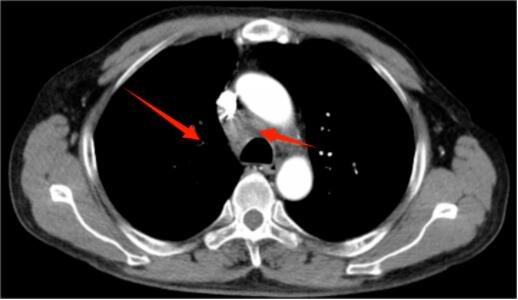

今年60岁的魏先生(化名),因“咳嗽、咳痰、胸痛、呼吸困难3月”到我院肿瘤科就诊。入院后,诊断为无驱动基因突变的晚期肺癌,具有化疗免疫联合治疗的适应症。

肿瘤科负责人、副主任医师王俊带领团队为魏先生行免疫治疗联合化疗后,影像资料显示肺部及纵隔病灶明显缩小,让魏先生的生活质量得到明显提高,临床症状完全消失。

治疗前